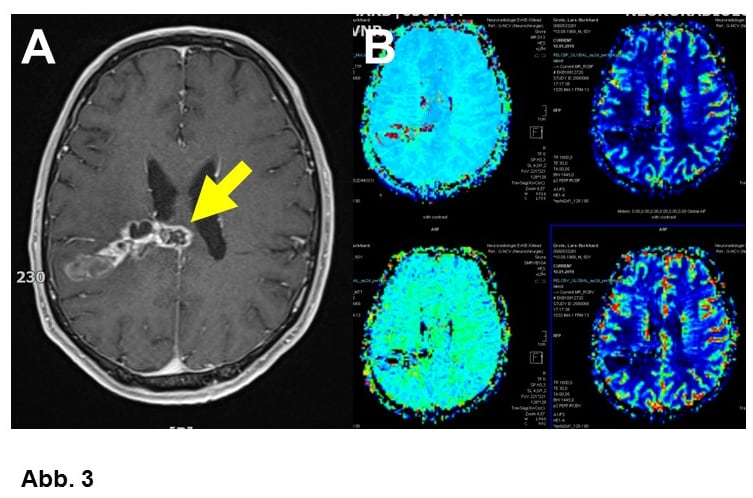

A. 50-jähriger Patient, bei dem das Routine-MRT ein Glioblastomrezidiv (Pfeil) zu zeigen scheint.

B. Das Perfusions-MRT passt besser zu einer Strahlenreaktion, d.h. zeigt im verdächtigen Bereich keine vergleichbaren Signalauffälligkeiten.